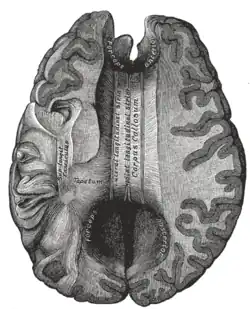

On either side of the corpus callosum, the fibers radiate in the white matter and pass to the various parts of the cerebral cortex; those curving forward from the genu into the frontal lobes constitute the forceps minor (also forceps anterior) and those curving backward from the splenium into the occipital lobes, the forceps major (also forceps posterior).[4] Between these two parts is the main body of the fibers, which constitute the tapetum and extend laterally on either side into the temporal lobe, and cover in the central part of the lateral ventricle. The tapetum and anterior commissure share the function of connecting left and right temporal lobes.

Thinner axons in the genu connect the prefrontal cortex between the two halves of the brain; these fibers arise from a fork-like bundle of fibers from the tapetum, the forceps minor. Thicker axons in the trunk of the corpus callosum interconnect areas of the motor cortex, with proportionately more of the corpus callosum dedicated to supplementary motor regions including Broca's area. The splenium communicates somatosensory information between the two halves of the parietal lobe and the visual cortex at the occipital lobe. These are the fibers of the forceps major.[12][13]